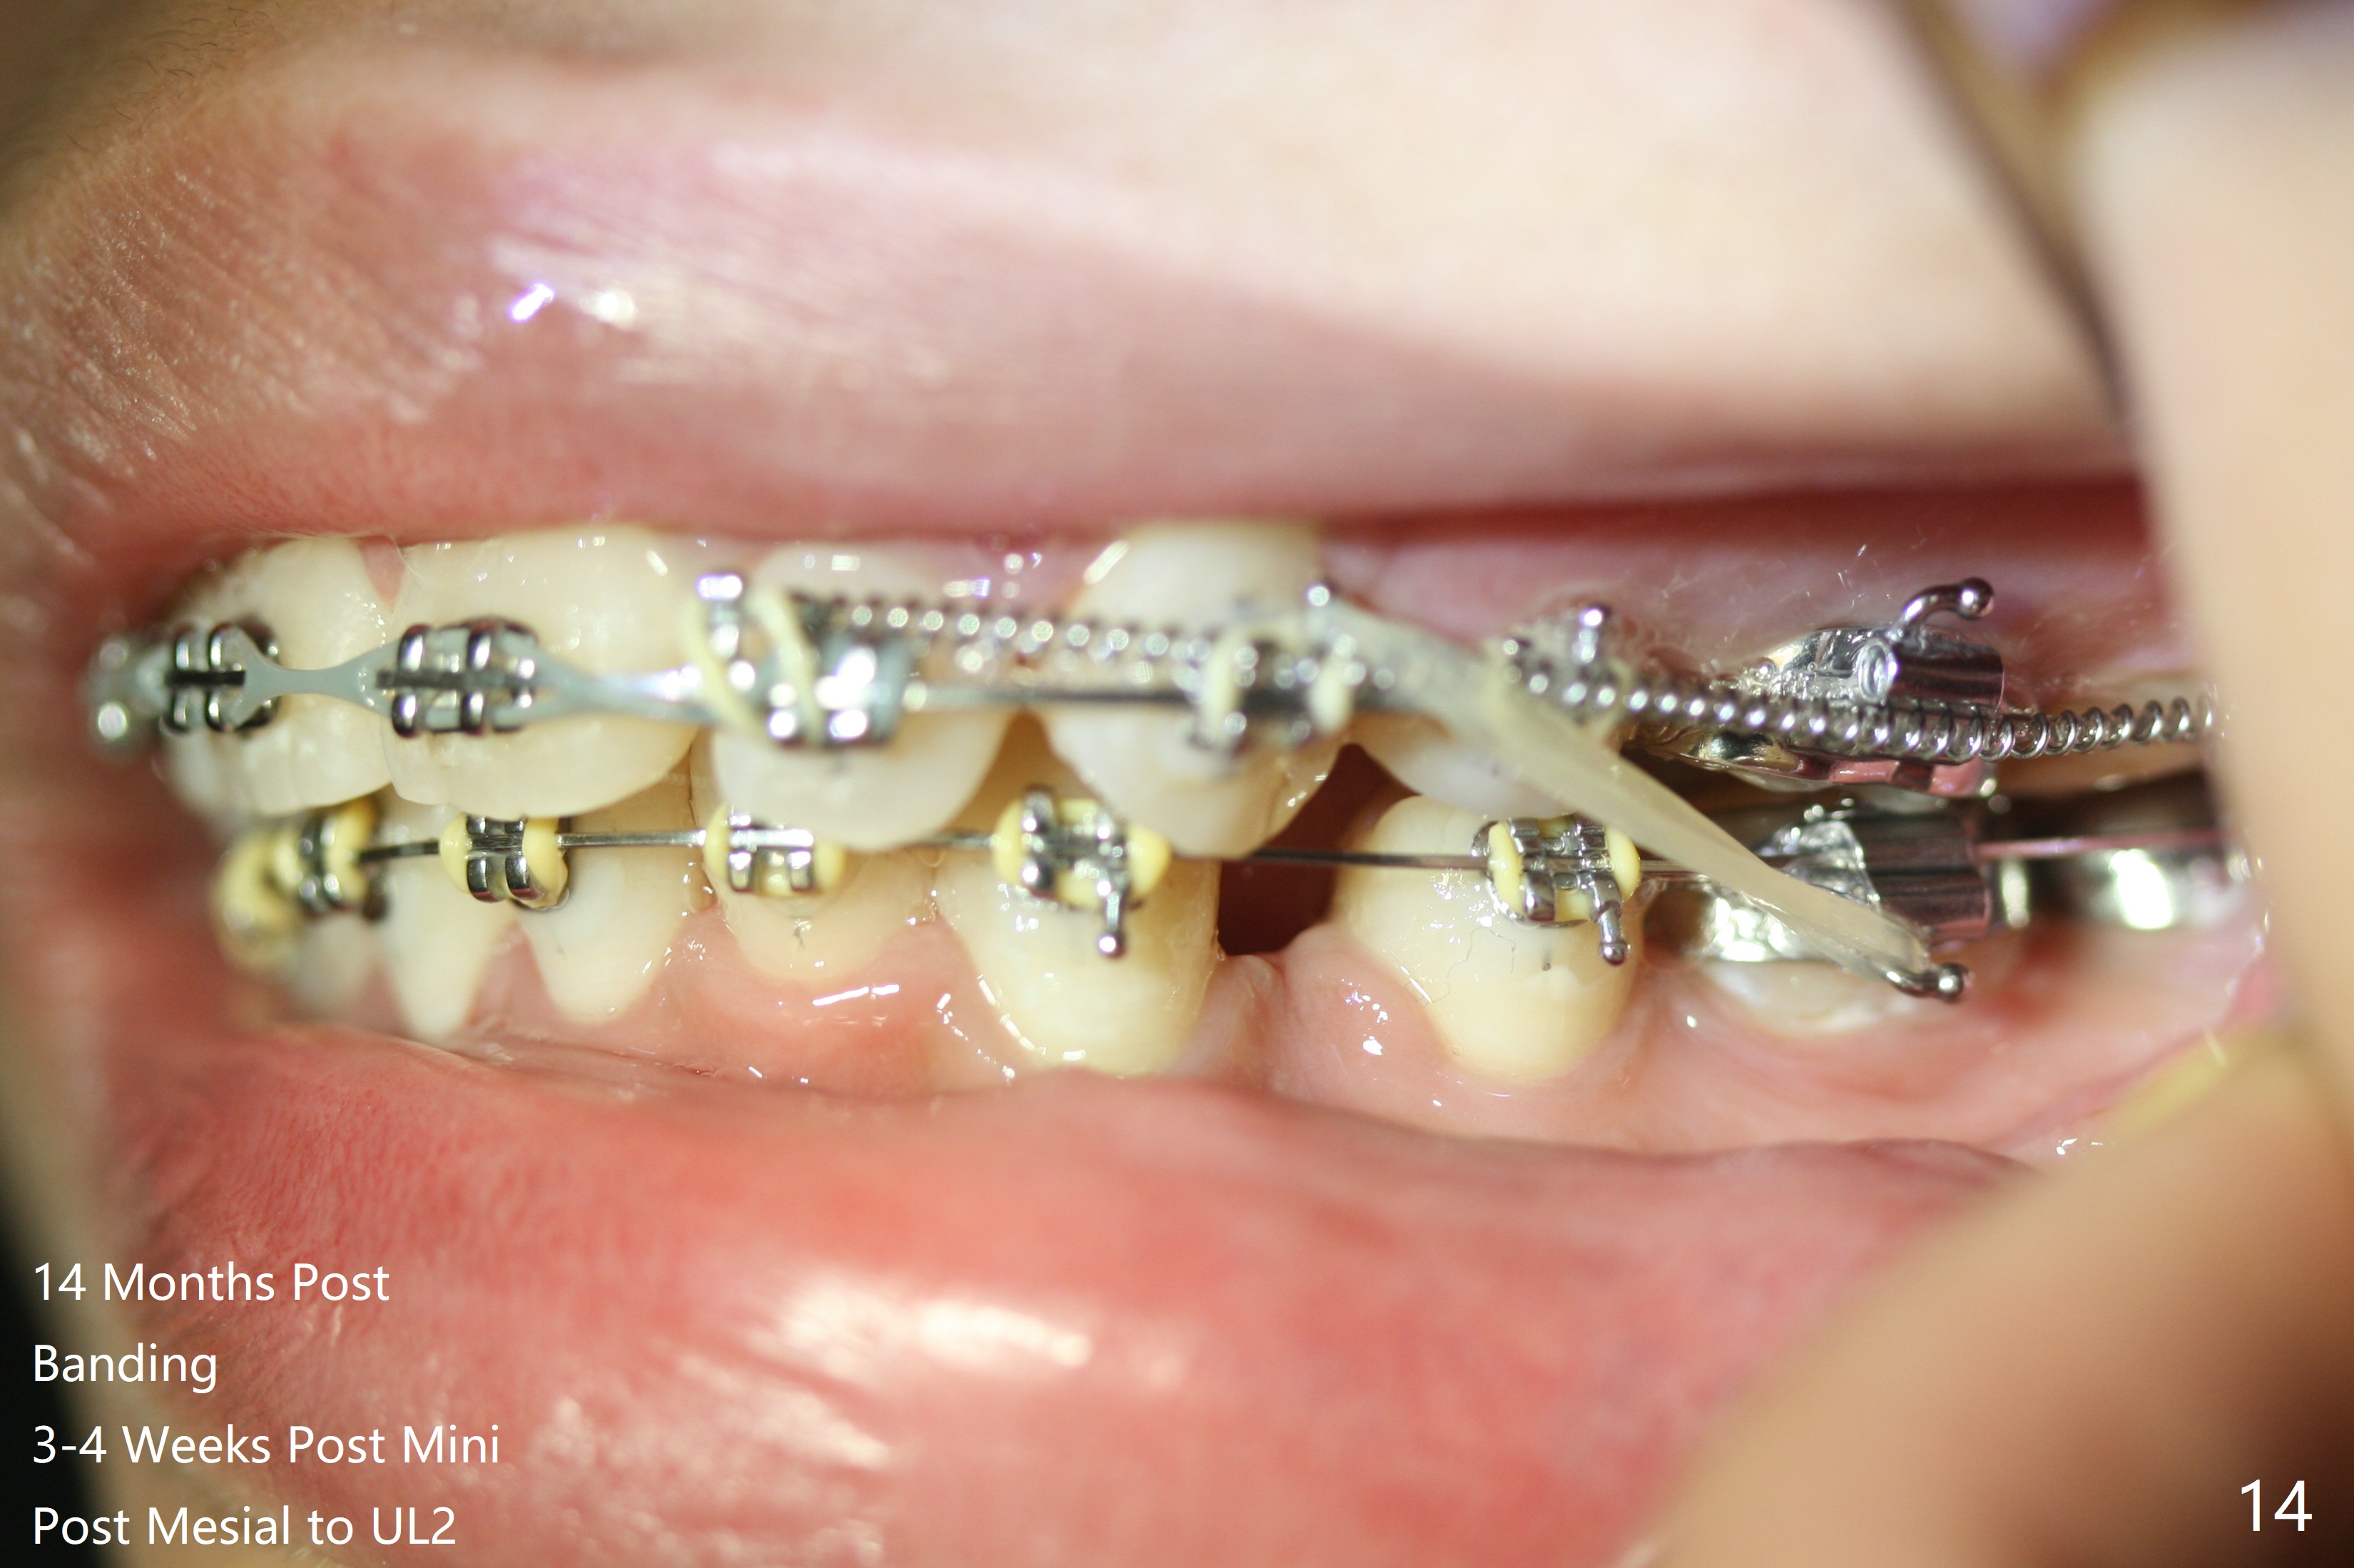

Thirteen months post banding, U dental midline apparently coincides with facial one, diastemata: UL2/3, UL6/7, L3-3, UL post detached, placed crimpable mini post mesial to UL2, closed spring UL2-7. Three-4 weeks later, diastema appears between UL1/2, while that of UL6/7 closes. Continue closed spring between UL2/7, while adding power chains U2-2 (Fig.12). To correct anterior overjet (Fig.13), Class II retraction is introduced bilaterally (Fig.14). After mesialization of LL3 (with Class I canine occlusion), L3-3 are being ligated as an anchor to mesialize LL5 (Fig.15). Occlusion appears to be Class II nearly 3 years post banding. Miniimplants are planned to distalize the upper dentition. Upper anterior PAs are taken to determine whether the roots of the upper anterior teeth have been resorbed. In fact, they are (Fig.16,17). Fortunately the anterior overjet does not look so severe. Orthodontic treatment should be terminated soon. Next case PAs should be taken prior to distalization.